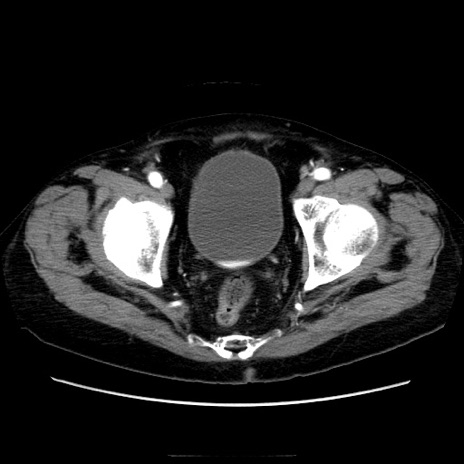

症例21(横断像)

【症例】70歳代男性

【主訴】腹痛

【現病歴】肝硬変・肝細胞癌にてかかりつけの方。約9時間前に食後より腹痛出現。症状が徐々に増悪し、嘔吐出現したため来院。

【既往歴】肝硬変、肝細胞癌(RFA、TACE後)

【身体所見】意識清明、表情苦悶様、BT 36℃、BP 129/78mmHg、P 88bpm、SpO2 97%(RA)、右上腹部から心窩部にかけて圧痛あり、反跳痛なし、筋性防御あり。

【データ】WBC 5800、CRP 0.16